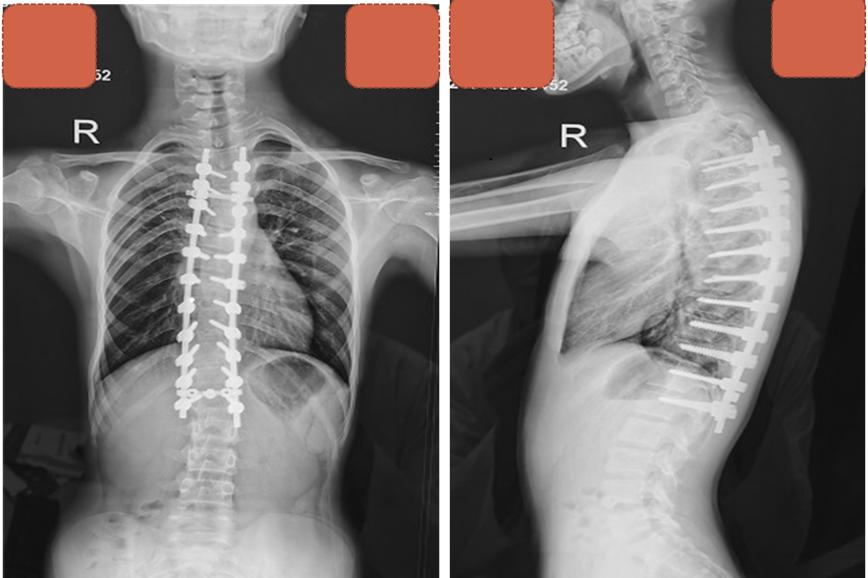

术后,对少年的脊柱功能和身体康复情况进行密切观测。术后一周,少年顺利出院。术后3个月复查,脊柱矫形效果维持良好,身高从153厘米升高到164厘米。

术后3个月复查侧弯矫形维持良好